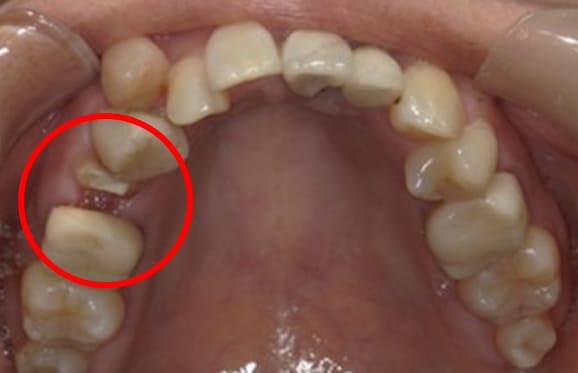

● 先天性の萌出方向異常を部分矯正で治療

藤沢デンタルオフィスの虫歯や破折で先天性の萌出方向異常を部分矯正で治療

01

02

03

04

05

06